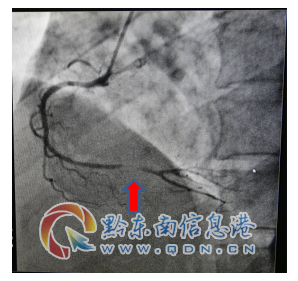

術前病變(箭頭所示)

該患者入院查肌鈣蛋白、心肌酶增高,復查心電圖提示“Q波加深、ST段下移較前明顯”,結合輔助檢查結果陳文海主任對患者病情診斷為急性心肌梗死,考慮患者合并有糖尿病、甲亢等多種病癥,病情緊急,需按照胸痛中心急性心肌梗死流程緊急處理。經過該院心血管內科專家的會診評估,認為及早行冠脈介入診療對患者是有益的。征得該患者及家屬的同意后,立即啟動導管室行冠脈造影檢查,造影提示右冠脈遠段重度狹窄病變,在李健民副主任醫師的指導下,心血管內科陳文海主任、楊文林醫師對患者繼續行藥物球囊擴張術,選擇支架植入為補救治療方案。冠脈介入過程謹慎細致,最后判斷冠脈藥物球囊擴張術對患者獲益更大后,予以藥物球囊擴張術,不需植入冠脈支架,造影復查嚴重狹窄病變處經藥物球囊擴張術處理后,殘余狹窄小于30%,達到治療效果。手術過程歷經不足半小時,成功開通狹窄病變的冠脈血管,TIMI血流3級,手術效果滿意,術后患者安返病房,未再出現胸痛癥狀。

術后藥物球囊擴張后